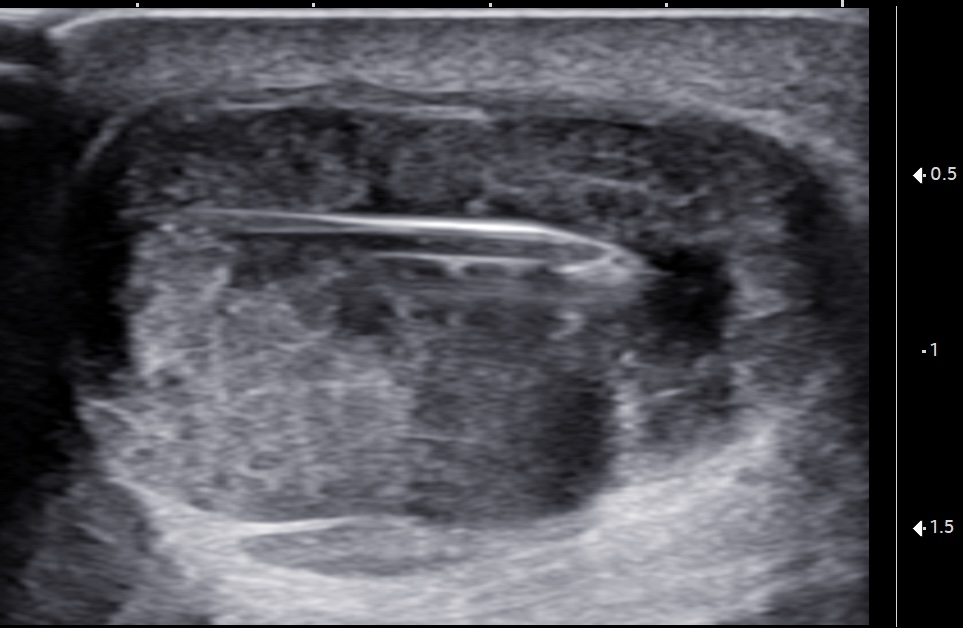

Unlabeled short-axis ultrasound image of the midportion Achilles tendon showing the ultrasound-guided cyst aspiration using an 18-gauge, 1.5-inch needle.